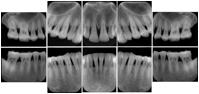

Intra-oral radiography typically involves acquisition of multiple images of various parts of the dentition. Many digital radiographic systems offer customized templates that are used for displaying the images in a study on the screen. These templates may also be referred to as mounts or view sets. The Structured Display Object represents a standard method of encoding and exchanging the layout and intended display of Structured Displays. A structured display object created in this manner could be stored with a study and exchanged with images to allow for complete reproduction of the original exam.

3. A dental provider wishes to capture a series of DICOM IO images for the patient’s dentition. The tooth morphology, teeth are divided into molars, premolars, canines and incisors, and a number of images for each jaw. The anatomic information was captured utilizing the triplet of schema. This standard code sequence is based on ISO 3950-2010, Dentistry - Designation system for teeth and areas of the oral cavity.

In most standard cases, images are oriented in structured layouts. These structured displays are useful to be shared between providers for reference purposes.

Table OO.1.1-1 shows structured display standard templates, where Viewset ID is based on the Japanese Society for Oral and Maxillofacial Radiology (JSOMR) classification provided by JIRA (Japan Medical Imaging and Radiological Systems Industries Association, www.jira-net.or.jp). Expected or typical teeth to be imaged location, region and designation codes are based on ISO 3950-2010, Dentistry - Designation system for teeth and areas of the oral cavity. For all the hanging protocols listed in OO.1.1-1, the value to use for Hanging Protocol Creator (0072,0008) is "JSOMR" and the value to use for Hanging Protocol Name (0072,0002) does not include "JSOMR" (e.g., "DL-S001A", not "JSOMR DL-S001A").